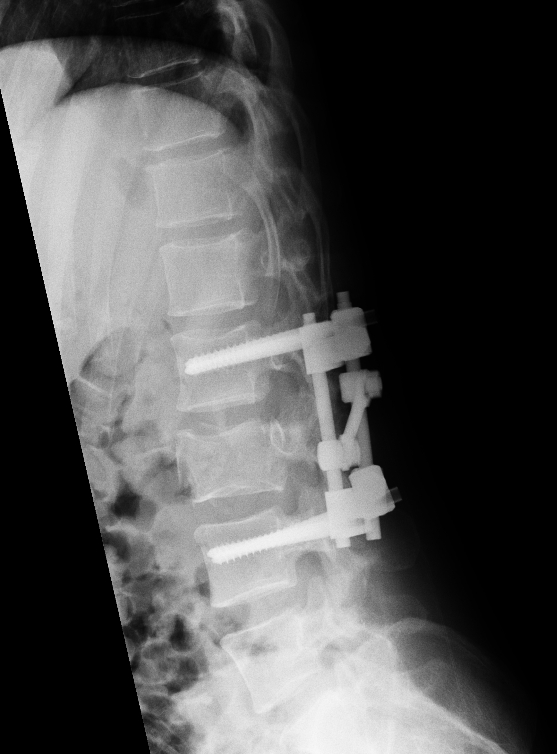

Příklad operační léčby poranění bederní páteře. Pacient se závažnou, tříštivou zlomeninou 3. bederního obratle sražení osobním vozem. Operační terapie ve dvou dobách, primárně zadní korekce a fixace transpedikulárním vnitřním fixátorem s odstraněním útlaku nervových struktur, následně po několika dnech přední náhrada těla L3 roztažitelným implantátem.